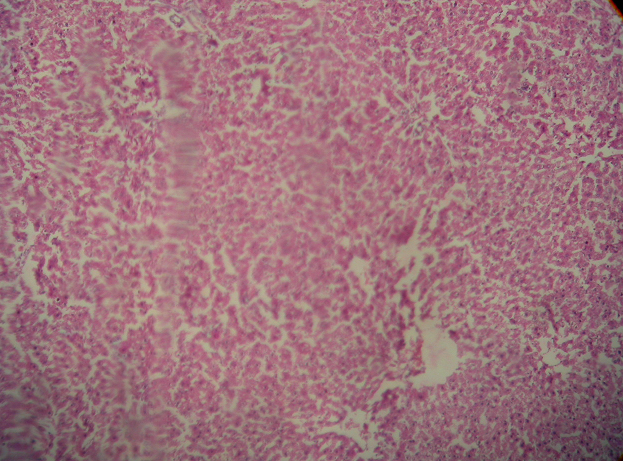

Histopathological examination of liver sections of control group (fig. 1) showed normal cellular architecture with distinct hepatic cells, sinusoidal spaces and central vein. In the liver sections of the rats intoxicated with paracetamol (fig. 2), there is disarrangement and degeneration of normal hepatic cells with intense centrilobular necrosis extending to mid-zone and sinusoidal haemorrhages and dilation.

The liver sections of the rats treated with silymarin and intoxicated with paracetamol (fig. 3) and rats treated with AESCR and AQESCR (low, medium and high doses) and intoxicated with paracetamol (fig. 4-9) showed less vacuole formation, reduced sinusoidal dilation, and less disarrangement and degeneration of hepatocytes, indicating marked regenerative activity. The intensity of centrilobular necrosis was less.

Fig. 1: Histology of normal hepatic tissue fig. 2: PCM induced damage in hepatic tissue

Fig. 3: Effect of Silymarin on PCM induced hepatic damage Fig. 4: Effect of AESCR (Low) dose on PCM induced hepatic damage

Fig. 5: Effect of AESCR (High) dose on PCM induced hepatic damage Fig. 6: Effect of AESCR (Med) dose on PCM induced hepatic damage

Fig. 7: Effect of AQESCR (Low) dose on PCM induced hepatic damage Fig. 8: Effect of AQESCR (Med) dose on PCM induced hepatic damage

Fig. 9: Effect of AQESCR (High) dose on PCM induced hepatic damage